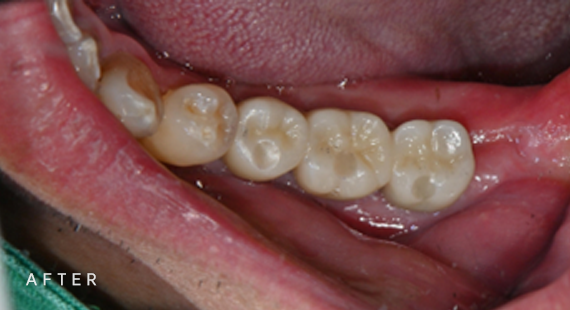

충치치료